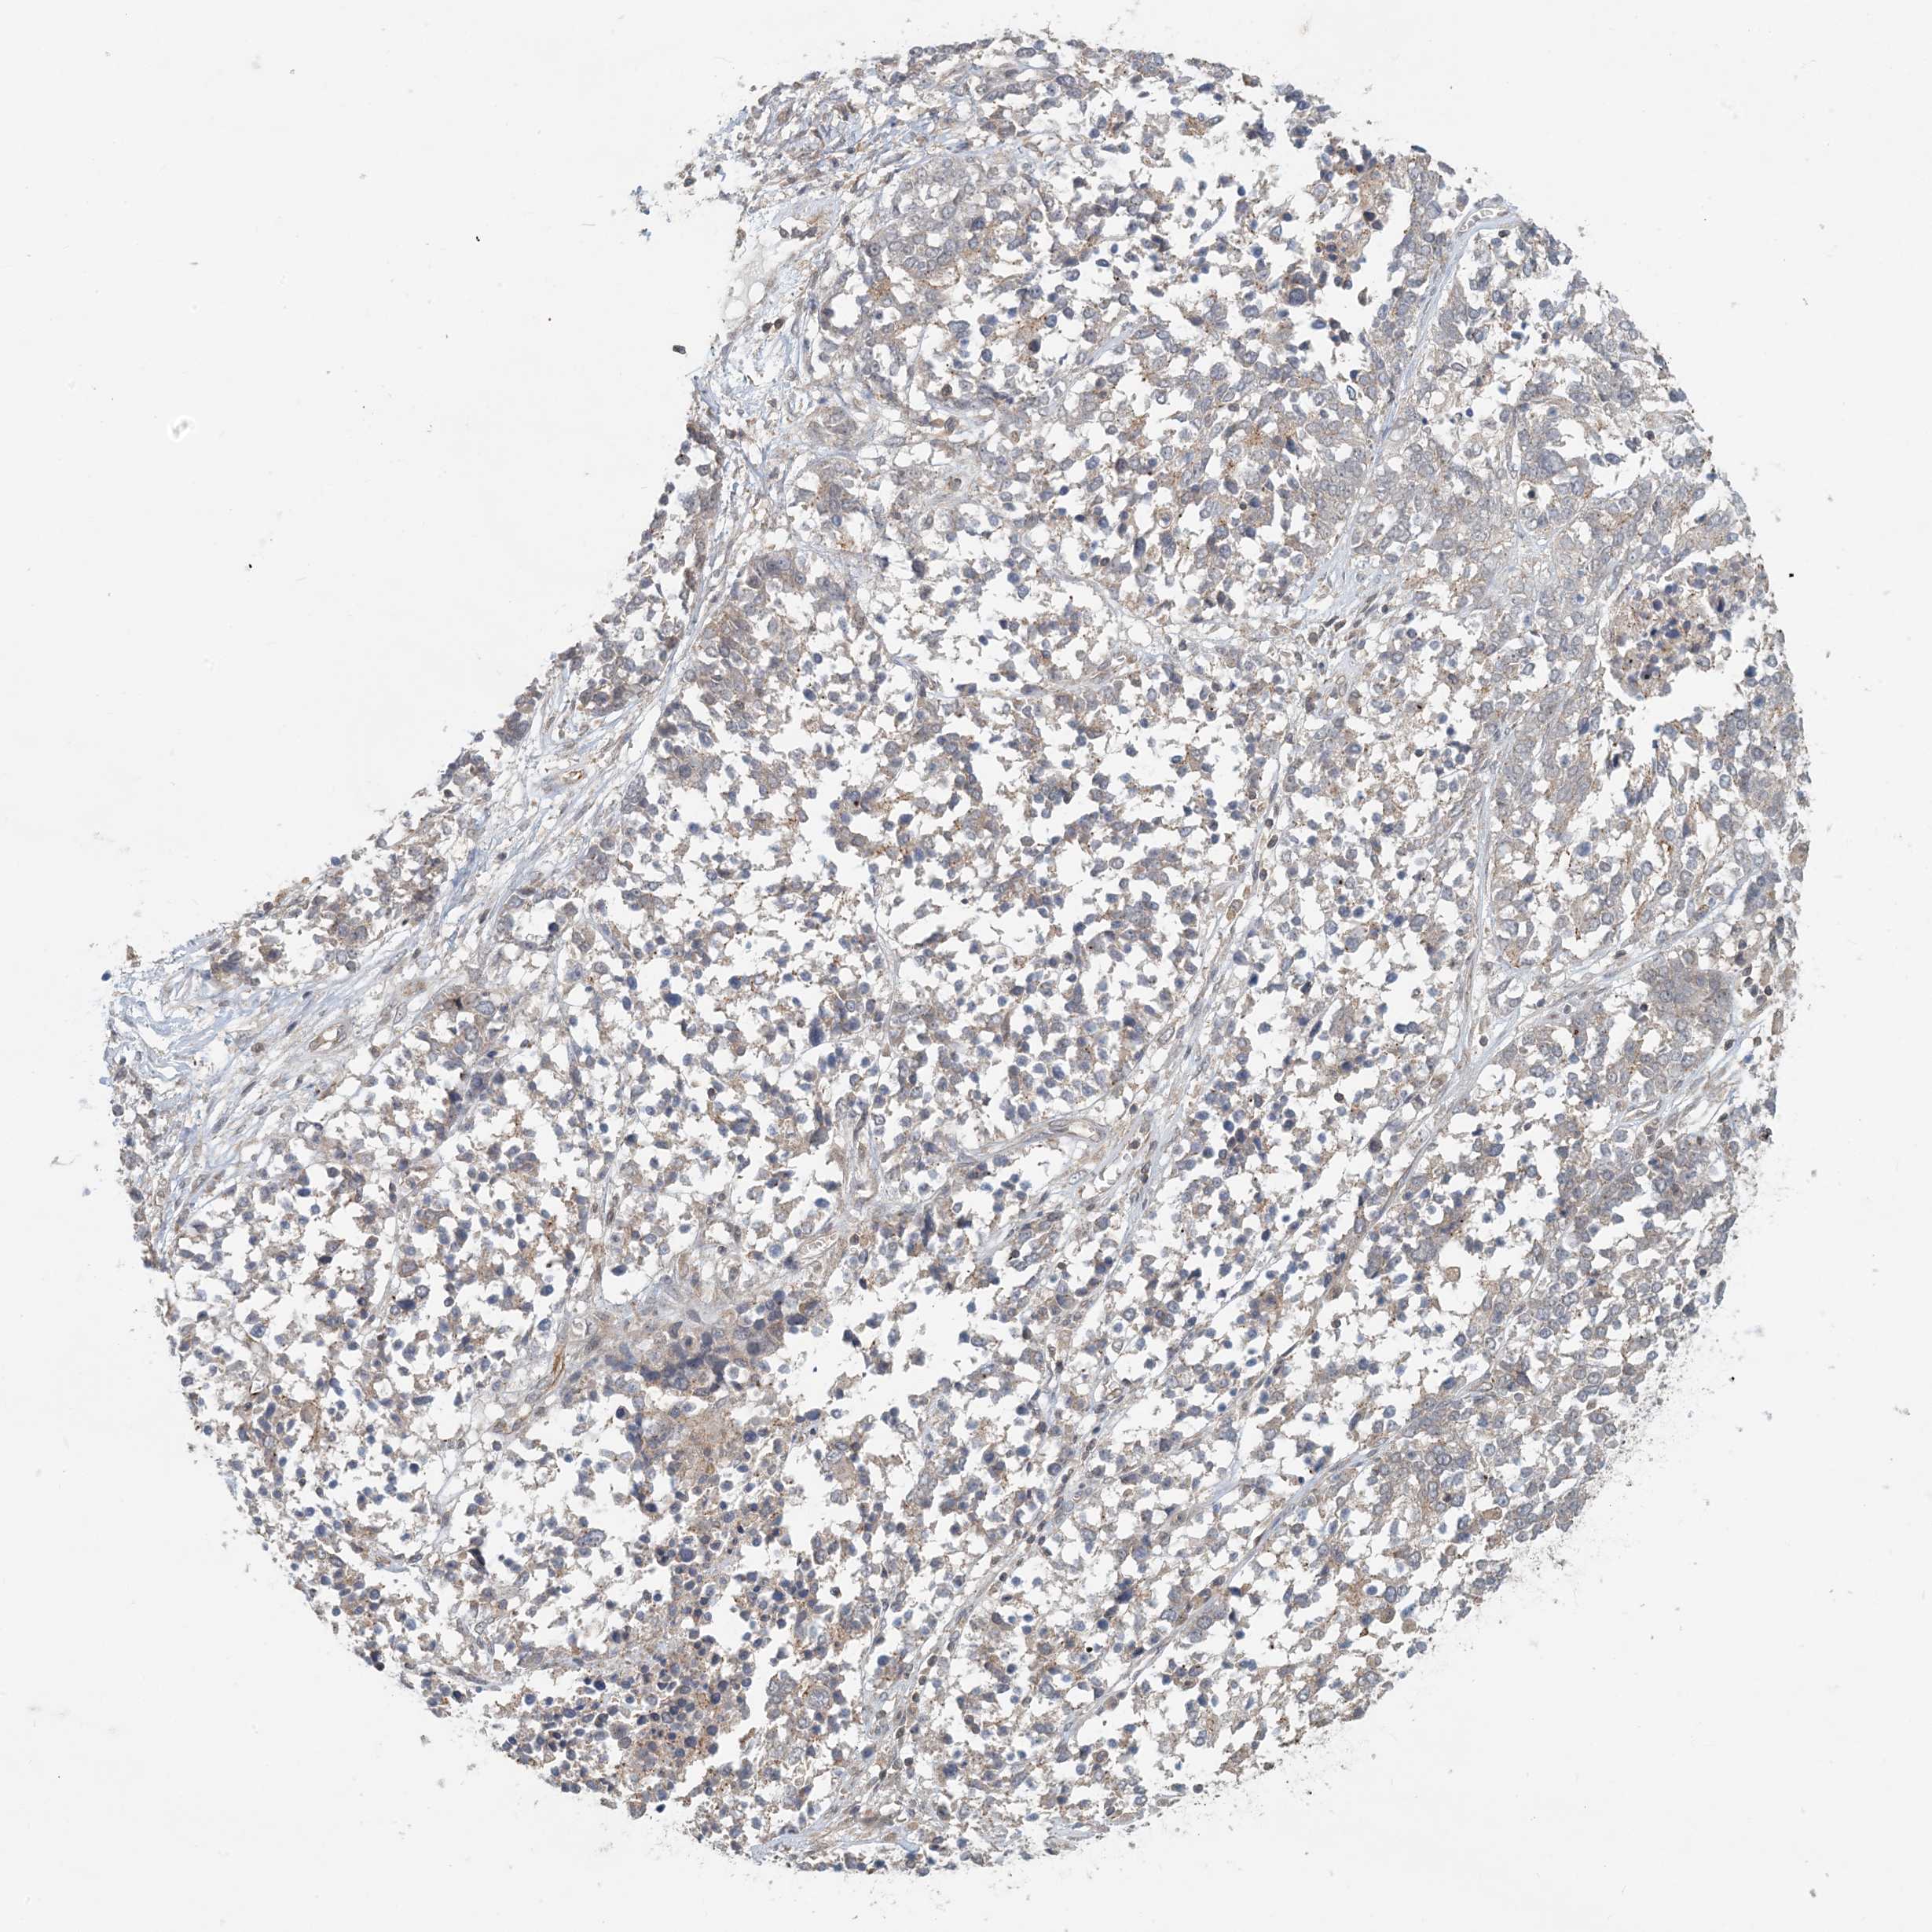

OVARIAN CANCER - Protein expressioni

A mouse-over function shows sample information and annotation data. Click on an image to view it in a full screen mode. Samples can be filtered based on level of antibody staining by selecting one or several of the following categories: high, medium, low and not detected. The assay and annotation is described here.

Note that samples used for immunohistochemistry by the Human Protein Atlas do not correspond to samples in the TCGA dataset.

Antibody stainingi

Antibody staining in the annotated cell types in the current human tissue is reported as not detected, low, medium, or high, based on conventional immunohistochemistry profiling in selected tissues. This score is based on the combination of the staining intensity and fraction of stained cells.

Each image is clickable and will lead to virtual microscopy that enables deeper exploration of all samples and also displays staining intensity scores, fraction scores and subcellular localization as well as patient and tissue information for each sample.

Antibody HPA034785

Antibody HPA034786

Cystadenocarcinoma, serous, NOS

Carcinoma, endometroid

Cystadenocarcinoma, mucinous, NOS

Carcinoma, NOS